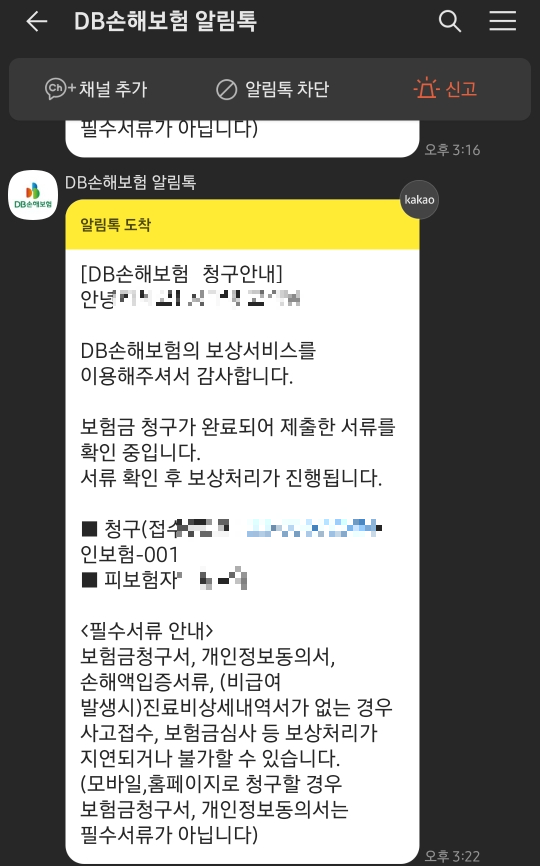

실비를 받기 때문에 서류

따로 챙겨달라고 했어요.

추가요금은 지불하지 않았고,

서류 잘 챙겨주셨어요.

영수증, 영수증, 수령증, 수취

진료비 상세 산정 내역

두 사진을 찍어서

삼성화재 앱에 로그인하고 사진만 첨부하면 된다.

그러면 바로 이렇게 문자가 와서

당일에 담당자가 배정됩니다.